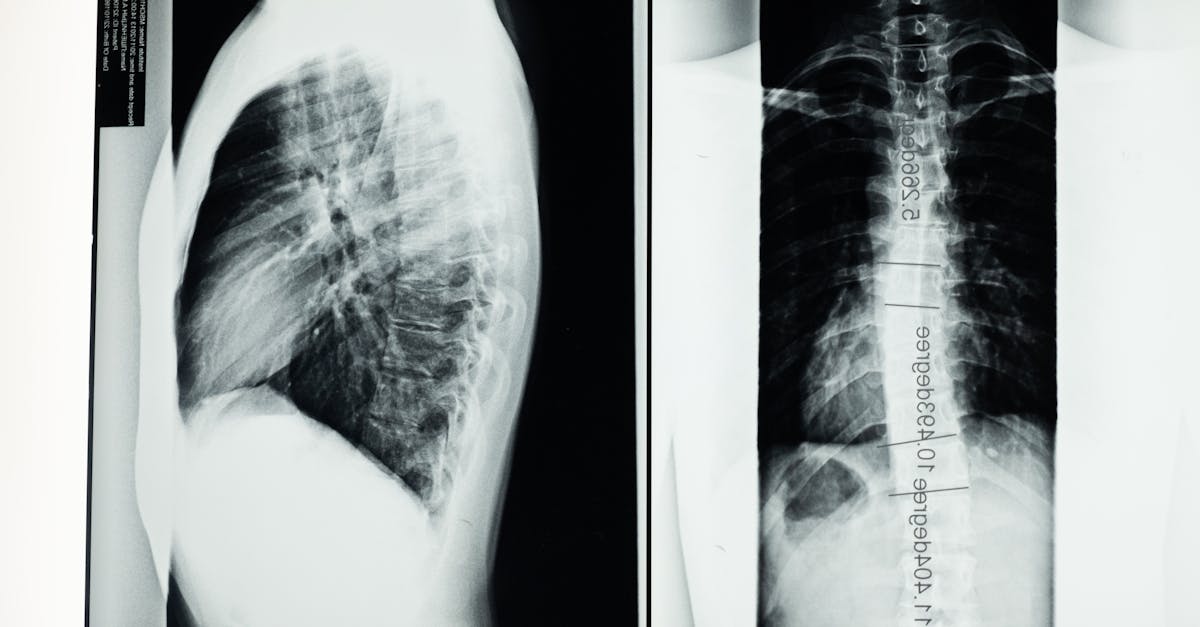

La décompression neurovertébrale est un traitement non invasif qui joue un rôle important dans l’amélioration de la qualité de vie des patients seniors. Cette technique vise à réduire la pression sur les disques intervertébraux et les nerfs, soulageant ainsi les doléances liées à des affections courantes telles que les douleurs lombaires et les sciatiques. Grâce à une meilleure circulation sanguine et à une réduction de l’inflammation, les seniors ressentent souvent une amélioration de leur mobilité et de leur flexibilité. En allégeant les tensions musculaires et en optimisant la posture, la décompression neurovertébrale permet également d’améliorer le confort quotidien et de diminuer les symptômes de douloureuse chroniques, contribuant ainsi à une vie plus active et épanouissante.

Un des principaux avantages de la décompression neurovertébrale pour les seniors est sa capacité à réduire la douleur. Les douleurs au dos, aux jambes ou au cou sont fréquentes chez les personnes âgées, souvent causées par des problèmes tels que les hernies discales ou les maladies dégénératives. En libérant la pression exercée sur les nerfs et les disques, cette technique permet de diminuer considérablement les douleurs, offrant un soulagement immédiat et durable.

Cette méthode repose sur une approche non invasive qui réduit la pression exercée sur les disques intervertébraux et les nerfs spinal. En relâchant cette pression, la circulation sanguine est améliorée, permettant aux tissus de se réparer plus efficacement. Pour les seniors, qui peuvent avoir une circulation sanguine altérée, cette amélioration est cruciale. En effet, une meilleure circulation favorise la régénération des cellules et réduit l’inflammation, contribuant ainsi à un rétablissement plus rapide et à un soulagement des symptômes douloureux.

Tout d’abord, la décompression neurovertébrale agit en réduisant la pression sur les disques intervertébraux et les nerfs, ce qui contribue à atténuer les douleurs chroniques souvent ressenties par les seniors. Cette diminution de la douleur permet aux patients de mieux gérer leur quotidien, en leur offrant un soulagement immédiat et en réduisant la nécessité d’analgésiques. Ainsi, les patients seniors peuvent retrouver un certain niveau de confort, améliorant leur bien-être général.